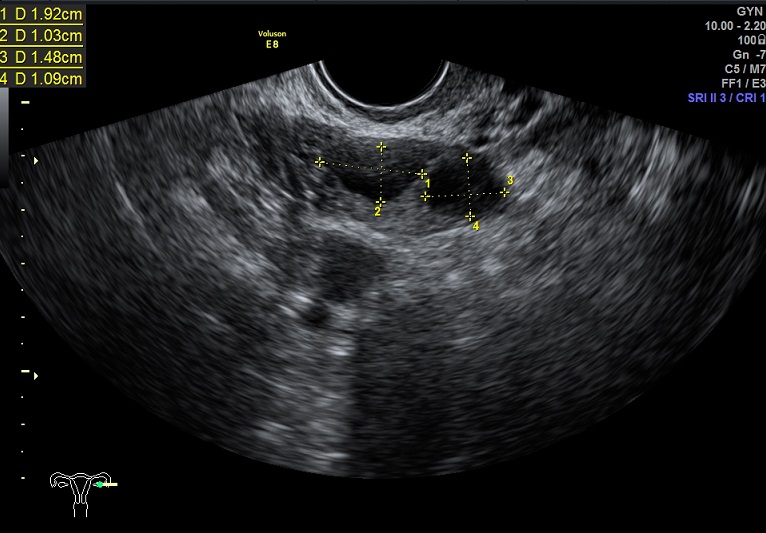

右卵巢: 大小3.3x2.0x1.1cm 体积:5.5 窦卵泡:5 卵巢间质血流:12.5cm/s RI:0.51